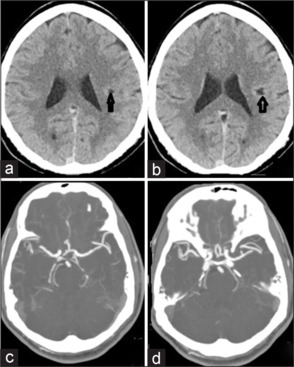

囊膜预警综合征(CWS)是一种罕见的疾病,其特征是复发性、典型的短暂性脑缺血发作(tia),影响面部、手臂和腿部,没有皮层受累。它与7天内发生全面中风的高风险有关。确切的病理生理机制和最佳管理策略仍有争议。区分CWS和渐强性tia至关重要,如果在全身再灌注治疗窗口内出现新的发作,则考虑再灌注治疗,以防止致残性卒中。我们报告一例53岁男性患者,因右偏瘫和面部虚弱持续1小时来到急诊科(ED)。在过去的7小时内,他经历了四次复发,典型发作,并被诊断为TIA,尽管在溶栓治疗窗口内。他开始双重抗血小板治疗,大剂量他汀类药物,并管理其他血管危险因素。然而,在24小时内,他的病情发展为完全中风,伴有严重的偏瘫和面部无力。磁共振成像证实左半球梗死,而计算机断层扫描血管造影正常。该病例强调了在ED中及时识别CWS的重要性,使卒中服务得以启动,并在适当时考虑再灌注治疗,以尽量减少致残性卒中的风险。

Capsular warning syndrome (CWS) is a rare condition marked by recurrent, stereotypical transient ischemic attacks (TIAs) affecting the face, arm, and leg, without cortical involvement. It is associated with a high risk of a full-blown stroke within 7 days. The exact pathophysiological mechanism and optimal management strategies remain debated. It is crucial to distinguish CWS from crescendo TIAs and consider reperfusion therapy if new episodes occur within the therapeutic window for systemic reperfusion, in order to prevent a disabling stroke. We present the case of a 53-year-old male who arrived at the emergency department (ED) with right hemiparesis and facial weakness lasting for 1 h. He had experienced four recurrent, stereotypical episodes over the past 7 h and was diagnosed with a TIA, despite being within the therapeutic window for thrombolysis. He was started on dual antiplatelet therapy, high-dose statins, and management of other vascular risk factors. However, within 24 h, his condition progressed to a complete stroke with severe hemiparesis and facial weakness. Magnetic resonance imaging confirmed infarction in the left hemisphere, while a computed tomography angiogram was normal. This case underscores the importance of prompt recognition of CWS in the ED, enabling activation of stroke services and the consideration of reperfusion therapy when appropriate, to minimize the risk of a disabling stroke.